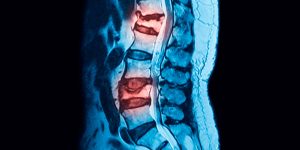

La hernia discal ocurre cuando el material del disco intervertebral presiona los nervios cercanos. El Dr. Valle alivia el dolor y recupera la movilidad mediante tratamientos avanzados.

Es el estrechamiento del canal vertebral que comprime la médula espinal o los nervios. El doctor ofrece soluciones efectivas para reducir la presión y mejorar la calidad de vida.